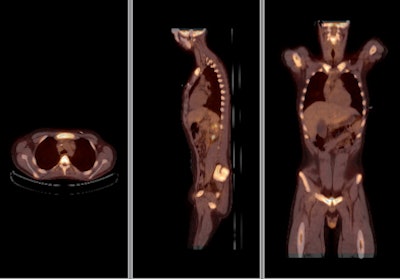

![]() |

| Above, PET and PET/CT fused data post-therapy for lymphoma. Below, PET and PET/CT fused data pretherapy for lymphoma. The images illustrate a patient's lymphoma staging to assess initial treatment strategy and follow-up study after initial treatment to plan subsequent treatment. The images were taken by Philips Healthcare's Gemini TF with time-of-flight. Images courtesy of Philips and University Hospitals Case Medical Center in Cleveland. |